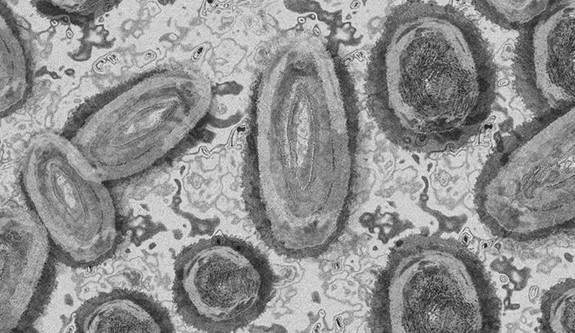

DSÖ uyardı: Afrika'da "M çiçeği" vakalarında artış yaşanıyor

Dünya Sağlık Örgütü (DSÖ), Afrika'da "M çiçeği (mpox)" vakalarında yaşanan artışa karşı uyararak bunun temel nedenlerinin belirlenmesi için yoğun araştırılmaların yapılması çağrısında bulundu.

Lewis, M çiçeği vakalarının artmaya devam etmesiyle bunun bir halk sağlığı tehdidi olmaya devam ettiğini vurgulayarak, yılbaşından bu yana dünya genelinde 3 bin 100'den fazla vaka rapor edildiğini söyledi.

"Yalnızca mayısta 26 ülkeden yaklaşık 600 doğrulanmış vaka DSÖ'ye bildirildi." ifadesini kullanan Lewis, özellikle Afrika'da M çiçeği vakalarında artış yaşandığını vurgulayarak bunun temel nedenlerinin tespit edilmesi için yoğun araştırmaların yapılması yönünde çağrıda bulundu.

Lewis, nisandan bu yana Güney Afrika'nın M çiçeği virüsünün bir varyantı olan "clad IIb" virüsüne bağlı 13 doğrulanmış vaka ve iki ölüm bildirildiğini belirtti.

Kongo Demokratik Cumhuriyeti'nin büyük bir salgınla karşı karşıya kalmaya devam ettiğini söyleyen Lewis, yalnızca 2024'te bildirilen 9 bin 291 M çiçeği vakasından 419'unun ölümle sonuçlandığını söyledi.

Lewis, Kongo Demokratik Cumhuriyeti'nde tespit edilen M çiçeği virüsü vakalarında ölüm oranın yaklaşık yüzde 5 olduğunu kaydetti.

Salgın nedeniyle daha çok çocukların yaşamını yitirdiğini kaydeden Lewis, Afrika'da M çiçeği vakalarında son zamanlarda görülen artışın ele alınmasının kritik bir ihtiyaç olduğunun da altını çizdi.